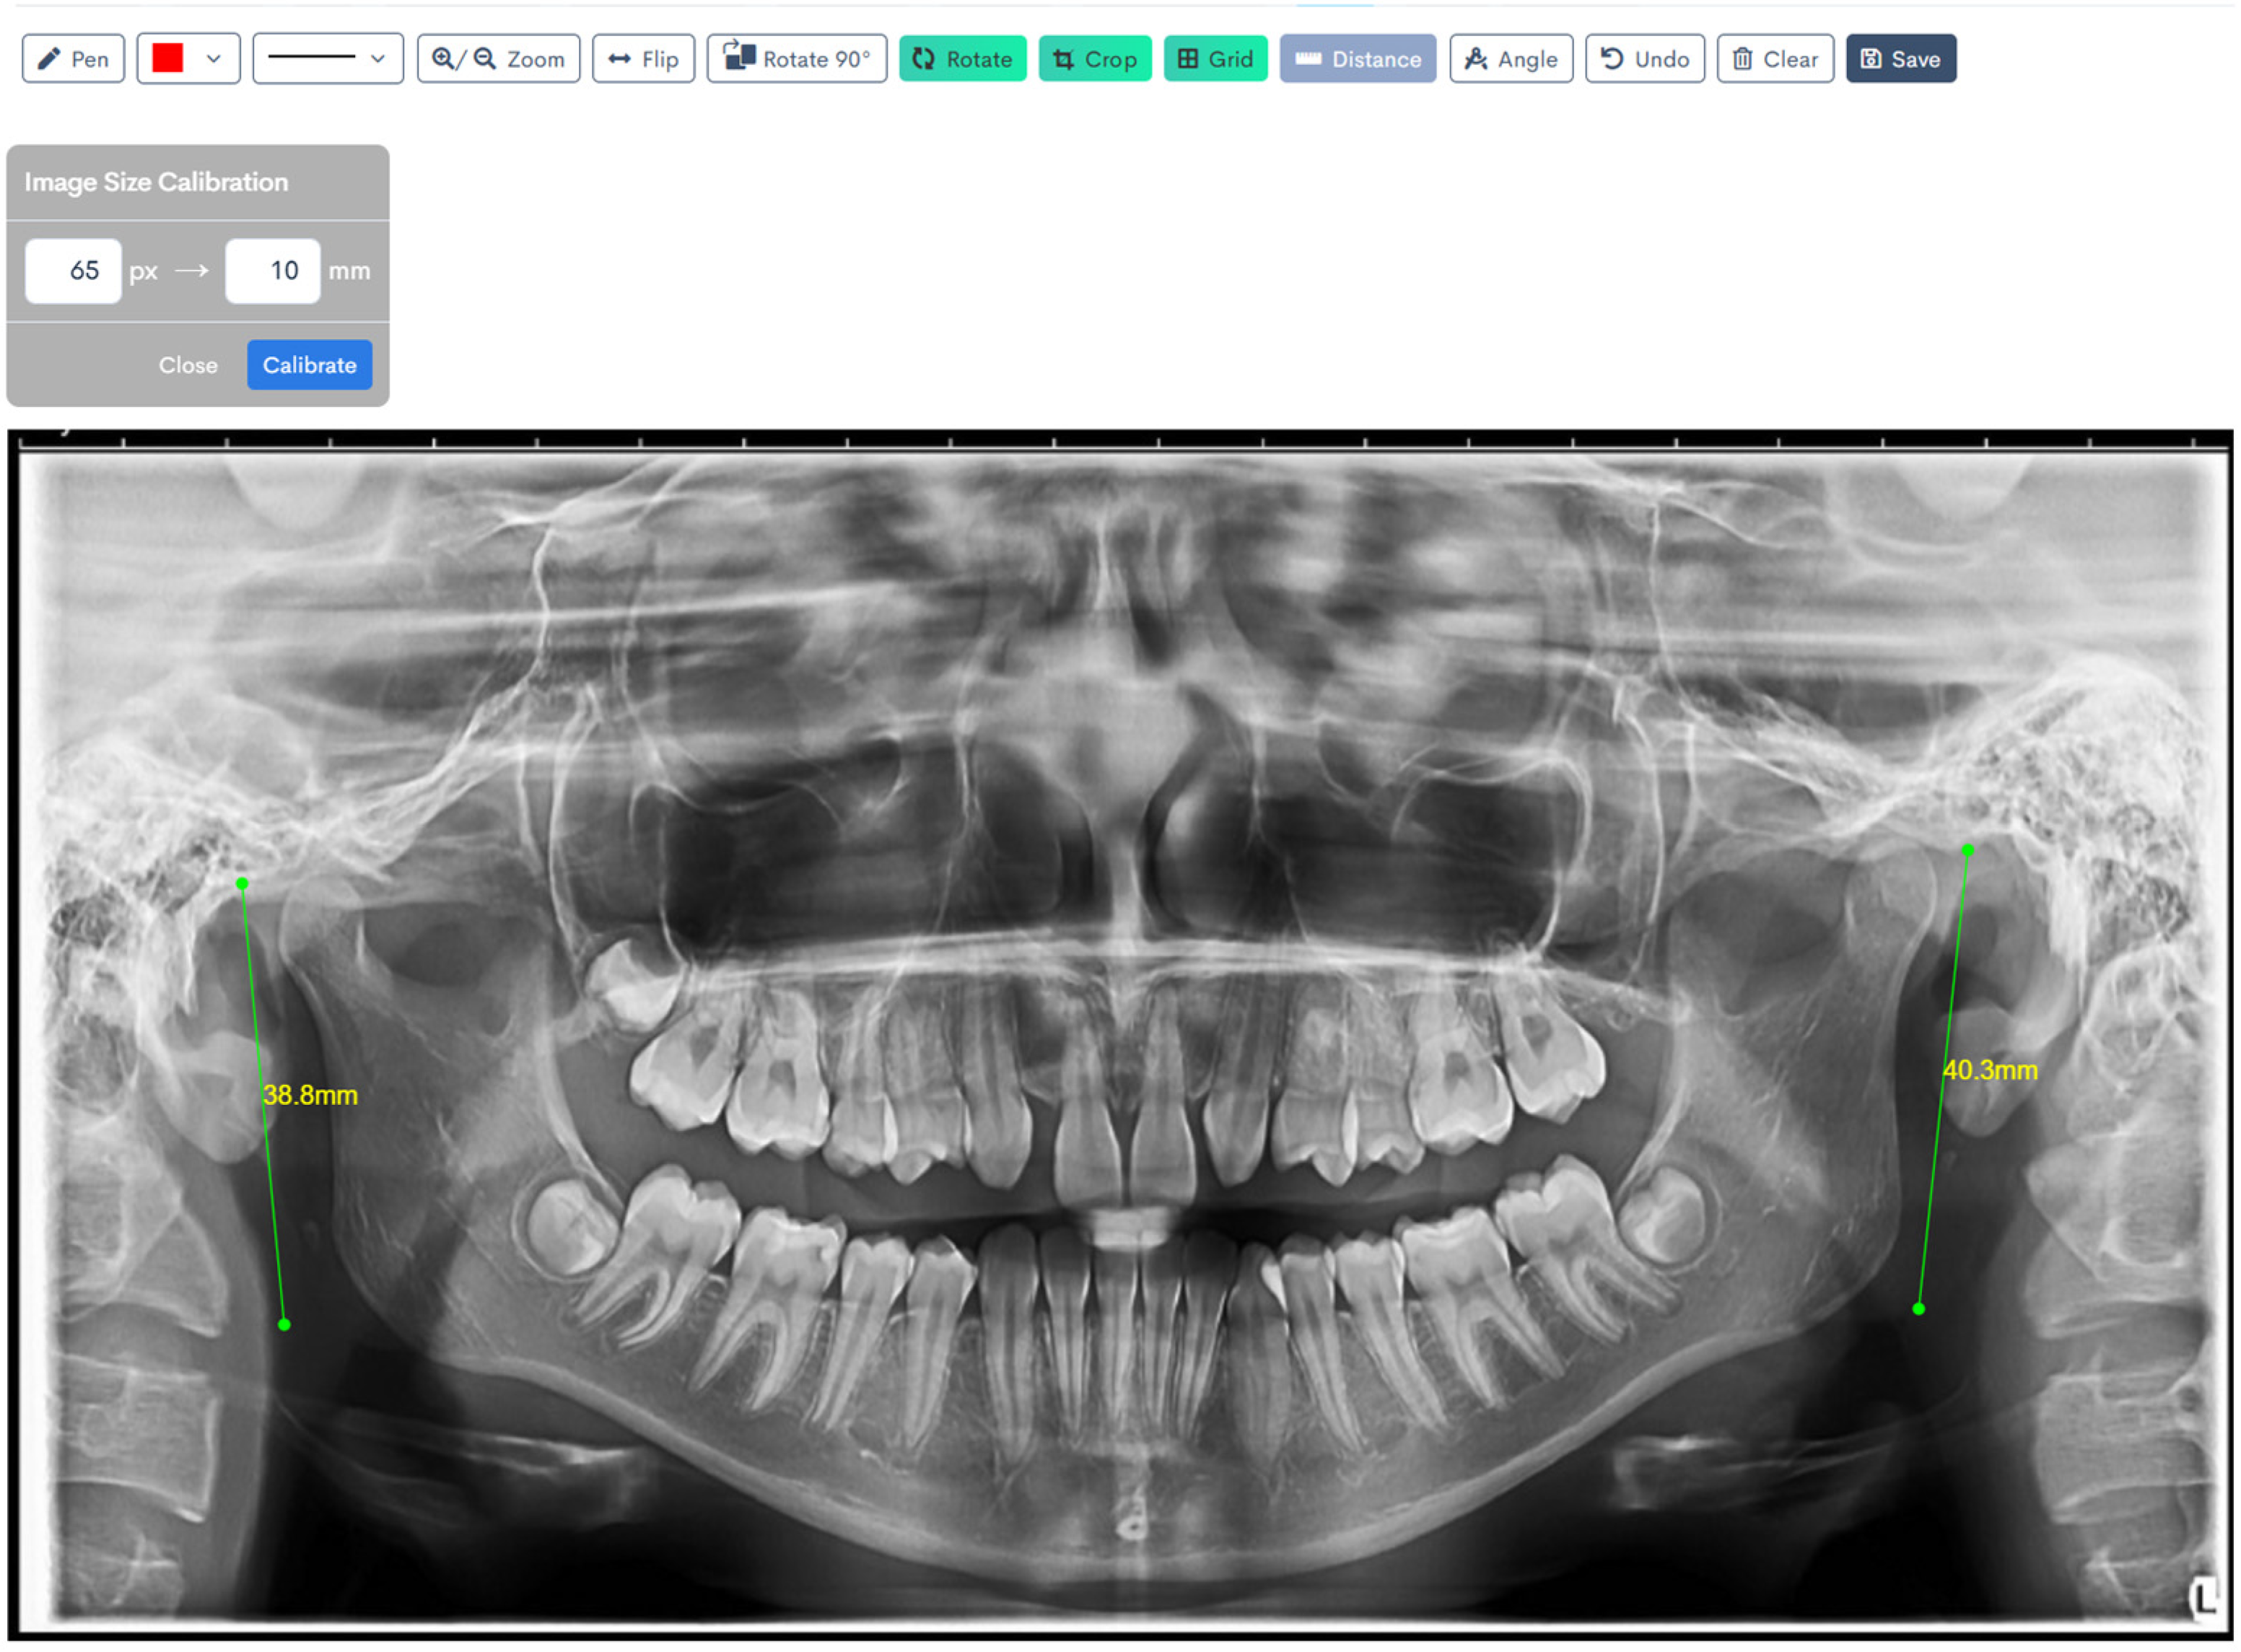

A calibration factor of 65 pixels was applied for all linear measurements performed on the panoramic radiographs [20]. The digital images, saved in JPEG format, were imported into WebCeph, an AI-powered orthodontic analysis platform patented by both the Korean and United States Intellectual Property Offices.

Figure 1, Figure 2, Figure 3, Figure 4, Figure 5 and Figure 6 illustrate the AI-assisted digital measurements exported from the WebCeph software, showing the identification of anatomical landmarks and linear or angular dimensions analyzed in this study.

Digital tracing of bilateral ramus heights performed on WebCeph using a panoramic radiograph. Ramus height was defined as the linear distance from the most superior point on the mandibular condyle to the most inferior point on the mandibular border. The left ramus height measured 38.8 mm, and the right ramus height measured 40.3 mm, as shown by the green lines with on-screen readouts (Figure 6).

Figure 6. Digital Tracing of Bilateral Ramus Heights in WebCeph. Co (condylion)—the most superior point on the mandibular condyle; Inf—the most inferior point on the mandibular border. Ramus height (Co–Inf) is represented by the green lines with on-screen readouts (left: 38.8 mm; right: 40.3 mm), illustrating bilateral measurement and comparison. Note: Images represent direct screenshots exported from the WebCeph AI platform. Landmarks and measurement lines were automatically generated and manually verified by the authors.